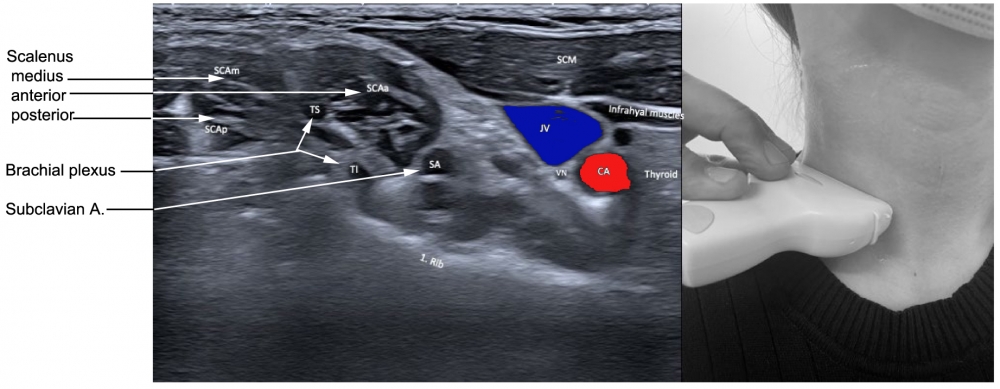

The muscle arises from the anterior tubercles of the transverse processes of C3-C6, and attaches onto the scalene tubercle, on the inner border of the first rib. It is located between the subclavian vein and the subclavian artery. The roots of the brachial plexus pass posterior to it. The phrenic nerve crosses its anterior surface.

Scalenus medius is the largest muscle of the scalenus group, and arises from the transverse processes of the cervical vertebrae and inserts into the superior portion of the first rib. This muscle can elevate the first rib or bend and rotate the neck. A needle can be placed into the scalenus medius muscle by palpating the belly of the muscle, in the floor of the posterior triangle, two finger breadths anterior to the anterior border of the trapezius muscle. At this point the muscle is just beneath the skin. The upper portion can be inserted by placing the needle just anterior to the lateral edge of the splenius capitis muscle to a depth of 1.5 to 3.0 cm.

Scalenus posterior arises from the posterior portion of the transverse processes of C5–6, passing medially and posteriorly to the scalenus medius, and inserts into the outer surface of the second rib, deep to the attachment of the serratus anterior. The scalenus posterior elevates the second rib or bends and slightly rotates the neck.

Figure 7. Trajectory of approach and relationships of the surrounding muscles to scalenus